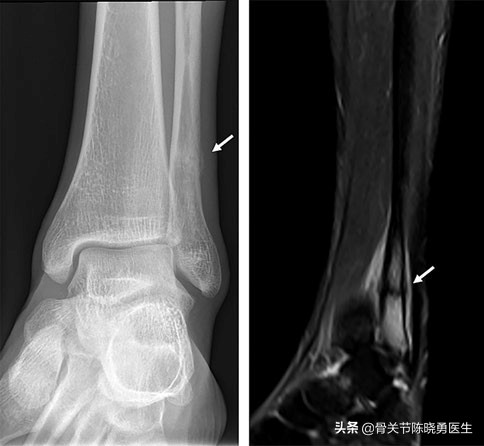

腓骨应力性骨折

有一些长跑或长途行走的患者,腓骨可能会因为受到长期、反复的压力而损伤。这种类型的损伤就称为应力性骨折。应力性骨折的疼痛可能会逐渐开始,随着运动量的增加而加重,休息后可以缓解。

通常,依靠X光片就可以对腓骨骨折做出诊断,但在应力性骨折等少数情况下,常规X线检查不会显示腓骨骨折。此时,医生除了检查受伤的部位以外,同时还会对膝关节和踝关节进行检查。如果腓骨临近的膝、踝关节的位置也存在异常,就会对腓骨骨折的治疗方案产生影响。